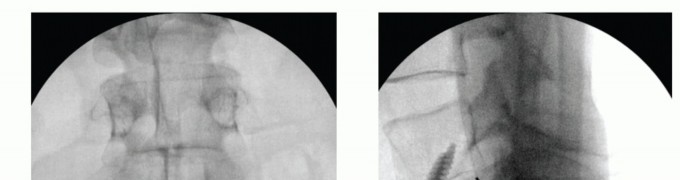

Once the discectomy has been completed, disc space distractors are inserted to gauge the size of the final implant (TECH FIG 3A). Appropriate distractor size can be gauged by comparing the operative level with a normal disc above or below. In addition, the interface between the distractor and the bony endplate should be less than 1 mm. This ensures good interference fit of the final device.

For threaded devices such as the lumbar tapered (LT) cage, a cannulated guide channel is inserted over the disc distractors. This working channel serves to prevent inadvertent migration of the great vessels into the disc space.

Endplate reamers are then inserted to appropriate depth as determined by lateral fluoroscopic imaging (TECH FIG 3B). Care should be taken to aim the reamer for the midportion of the disc space posteriorly on lateral fluoroscopy rather than through one endplate or the other.

- TECH FIG 3 • A. Lateral radiograph showing a radiopaque disc distractor within the intervertebral disc. The distractor approximates the height of the disc space above (L3-L4) and there is at most 1 mm of space between the intervertebral endplate and the distractor. B. Lateral radiograph showing reaming of the intervertebral channel for the anterior interbody device. Because the vertebral body is shallower in the AP plane away from the midline, reaming should stop shy of the posterior vertebral body line, as shown. C. Lateral radiograph showing threaded cage entry into the disc space. The cage is directed parallel to the vertebral endplates. (continued)

Final threaded implants are then screwed into the appropriate depth and orientation (TECH FIG 3C,D). The first cage (in a dualcage system) is inserted in the same trajectory as the reamers, and lateral fluoroscopic imaging during cage placement ensures that the cage is not placed too anteriorly or posteriorly. The cage should not be inserted beyond the depth of the reamer or else

the threads will strip and the cage will lose a large percentage of its fixation strength.

Saving the C-arm image of the final reamer depth allows the surgeon to reference this image when inserting the cage.

- TECH FIG 3 • (continued) D. Final cage placement should not extend beyond the depth of the reamer. E. Lateral radiograph showing final cage placement. The overlapping pedicles confirm true lateral positioning. F. AP radiograph showing parallel positioning of paired cages.

The second cage is inserted using the first cage as a reference for trajectory and depth. Final images should be true AP and lateral projections showing the cage devices to be in good position. Overlapping pedicles on the lateral image will appear sharp, confirming true lateral positioning (TECH FIG 3E,F).